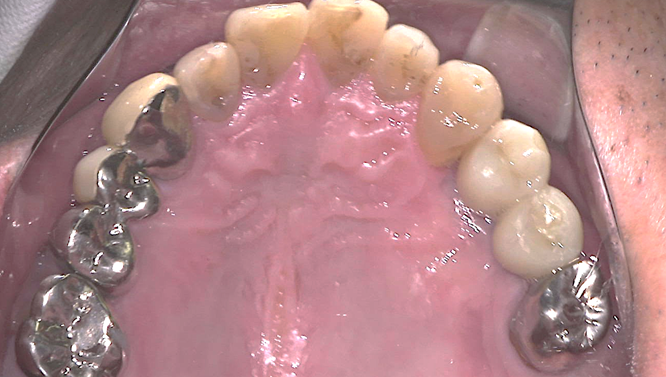

予定通りジルコニアクラウンにて、インプラント修復が行えました。